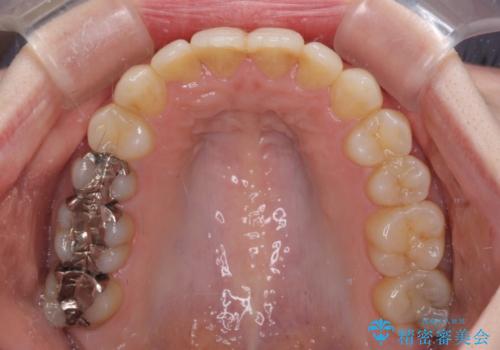

前歯のデコボコを改善 目立たないワイヤー矯正

治療途中で出産されたこともあり、当初予定よりも終了までに期間がかかってしまいました。

舌を前方に突出する癖があったため、上下前歯がなかなか接触しなかったことも治療期間が伸びた要因です。